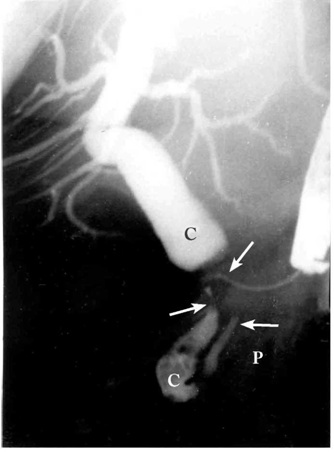

4.ERCP (Endoscopic retrograde cholangiopancreatography) - אם דרכי המרה אינן מורחבות, אפשר לבצע ERCP ולהדגים את החסימה בדרכי המרה, או פתולוגיה בצינור הלבלב (תצלום 27.9).

5. אנגיוגרפיה - מדגימה את השאת, בייחוד אם היא וסקולרית מאוד, או דחיקה של כלי דם בשאתות שאינן וסקולריות. התפתחות ה-CT הספיראלי המאפשר היום לבצע שחזור כלי דם של הלבלב והכלים הסמוכים לו, הורידה את ההוריות לשימוש באנגיוגרפיה בצורה דרסטית.